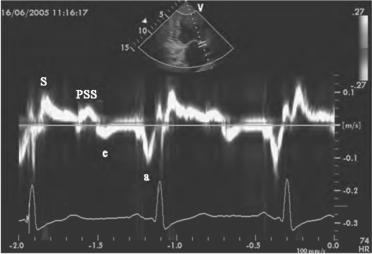

1.15.2第二节 多普勒组织成像

1.15.2.1一、多普勒组织成像的基本原理

1.15.2.2二、DTI的显示方式

1.15.2.3三、检查方法和常用指标

1.15.2.4四、DTI的临床应用